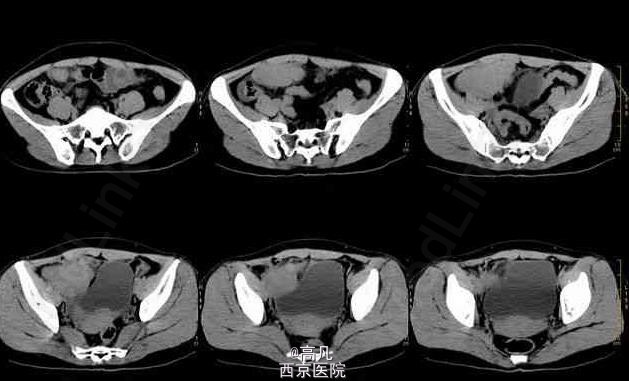

患者有周期性尿频、尿痛、血尿 辅查CT:右下腹可见囊实性不规则形肿块,实性为主。增强扫描不规则增厚的囊壁,内有多个大小不等囊变坏死区。